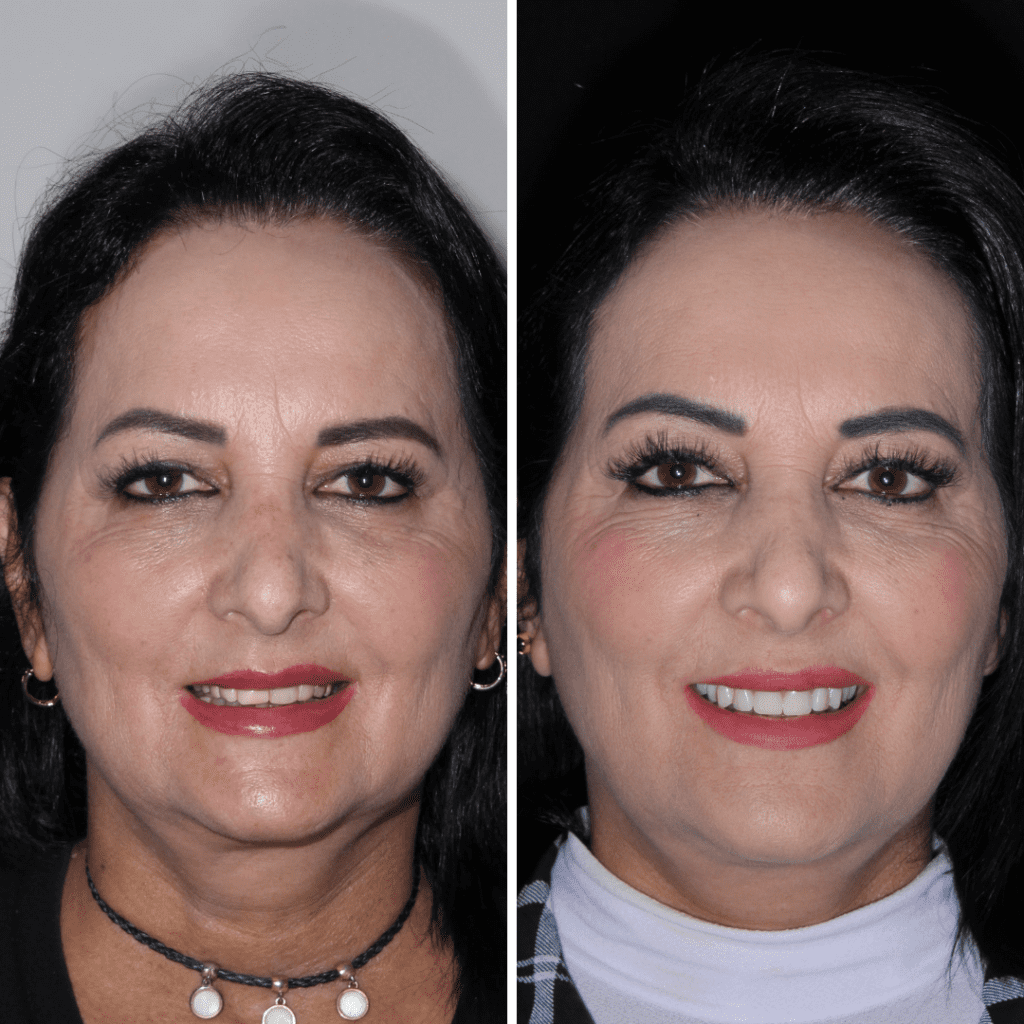

A ponte fixa sobre implante é indicado para pessoas que perderam alguns dentes intercalados ou da mesma região da boca. Realizar um tratamento com implante parcial é uma alternativa muito mais eficiente do que uma ponte convencional.

Os dentes presos em implantes dentais oferecem melhores resultados estéticos (não possui grampos metálicos) e dessa maneira impedem a reabsorção óssea.

Possibilita a sensação mais próxima possível de dentes naturais que a odontologia moderna oferece.